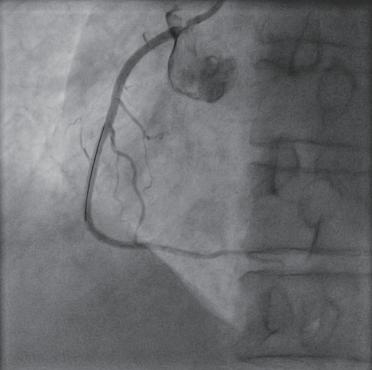

(4)退出支架球囊,以高压球囊再次扩张支架,使支架与血管壁紧密贴合,再次造影(图1-2-2),若显示血管腔通畅,血流恢复正常,血管壁完好,无造影剂潴留、渗出,冠状动脉各分支完好无影响,患者不适症状减轻或无不适,则撤出各导丝及导管,予桡动脉压迫止血器压迫穿刺口,手术结束,护送患者安返病房。

图1-2-2 右冠状动脉支架植入后造影